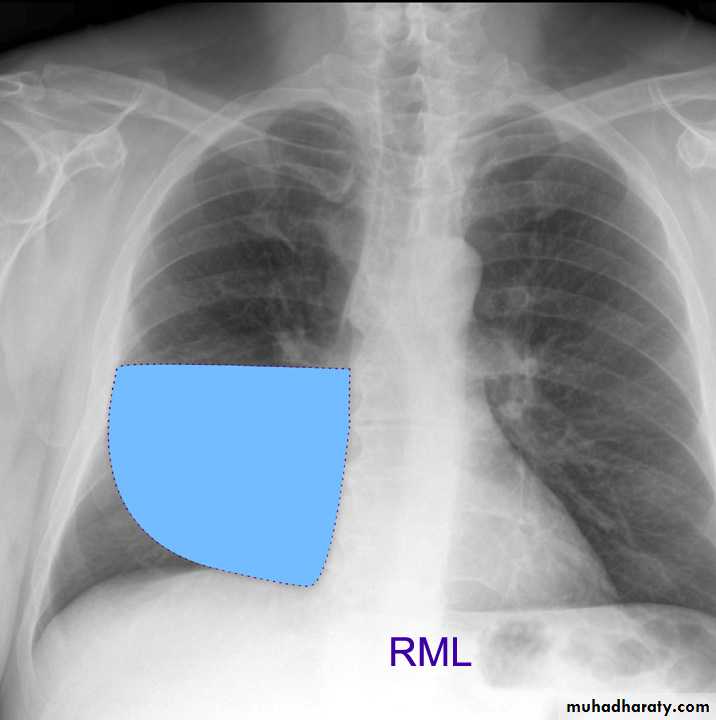

Lung Anatomy

Zonal anatomyLobar anatomy

Rt lung divided to 3 lobes (upper , middle & lower )

Transverse fissure separate the upper lobe from middle lobeOblique fissure separates the upper & middle from lower lobe .

Rt middle lobe